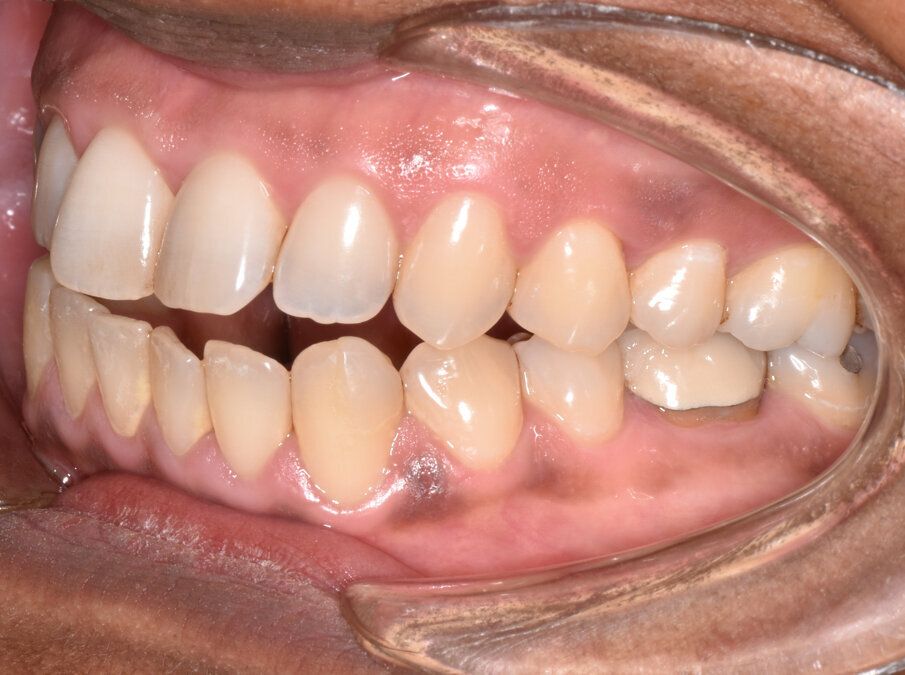

A 56-year-old female patient presented with a Class III malocclusion, anterior crowding and a 2-3 mm anterior open bite. Clinical photographs showed an ideal incisor display upon smiling. The panoramic film was unremarkable, and the lateral cephalometric film revealed a negative 1 mm overjet. (Figs. 1 to 10)

The treatment plan for this patient involved upper molar intrusion without the use of TADS in order to achieve counterclockwise rotation of the mandible and closure of the anterior open bite. Class III inter-arch elastics were prescribed to establish Class I molar and canine relationships and achieve proper overjet.

Button cut-outs were prescribed on the upper first molars, and elastic hooks on the lower canines to attach 5/16, 4.5-ounce Class III inter-arch elastics. (Fig. 12)